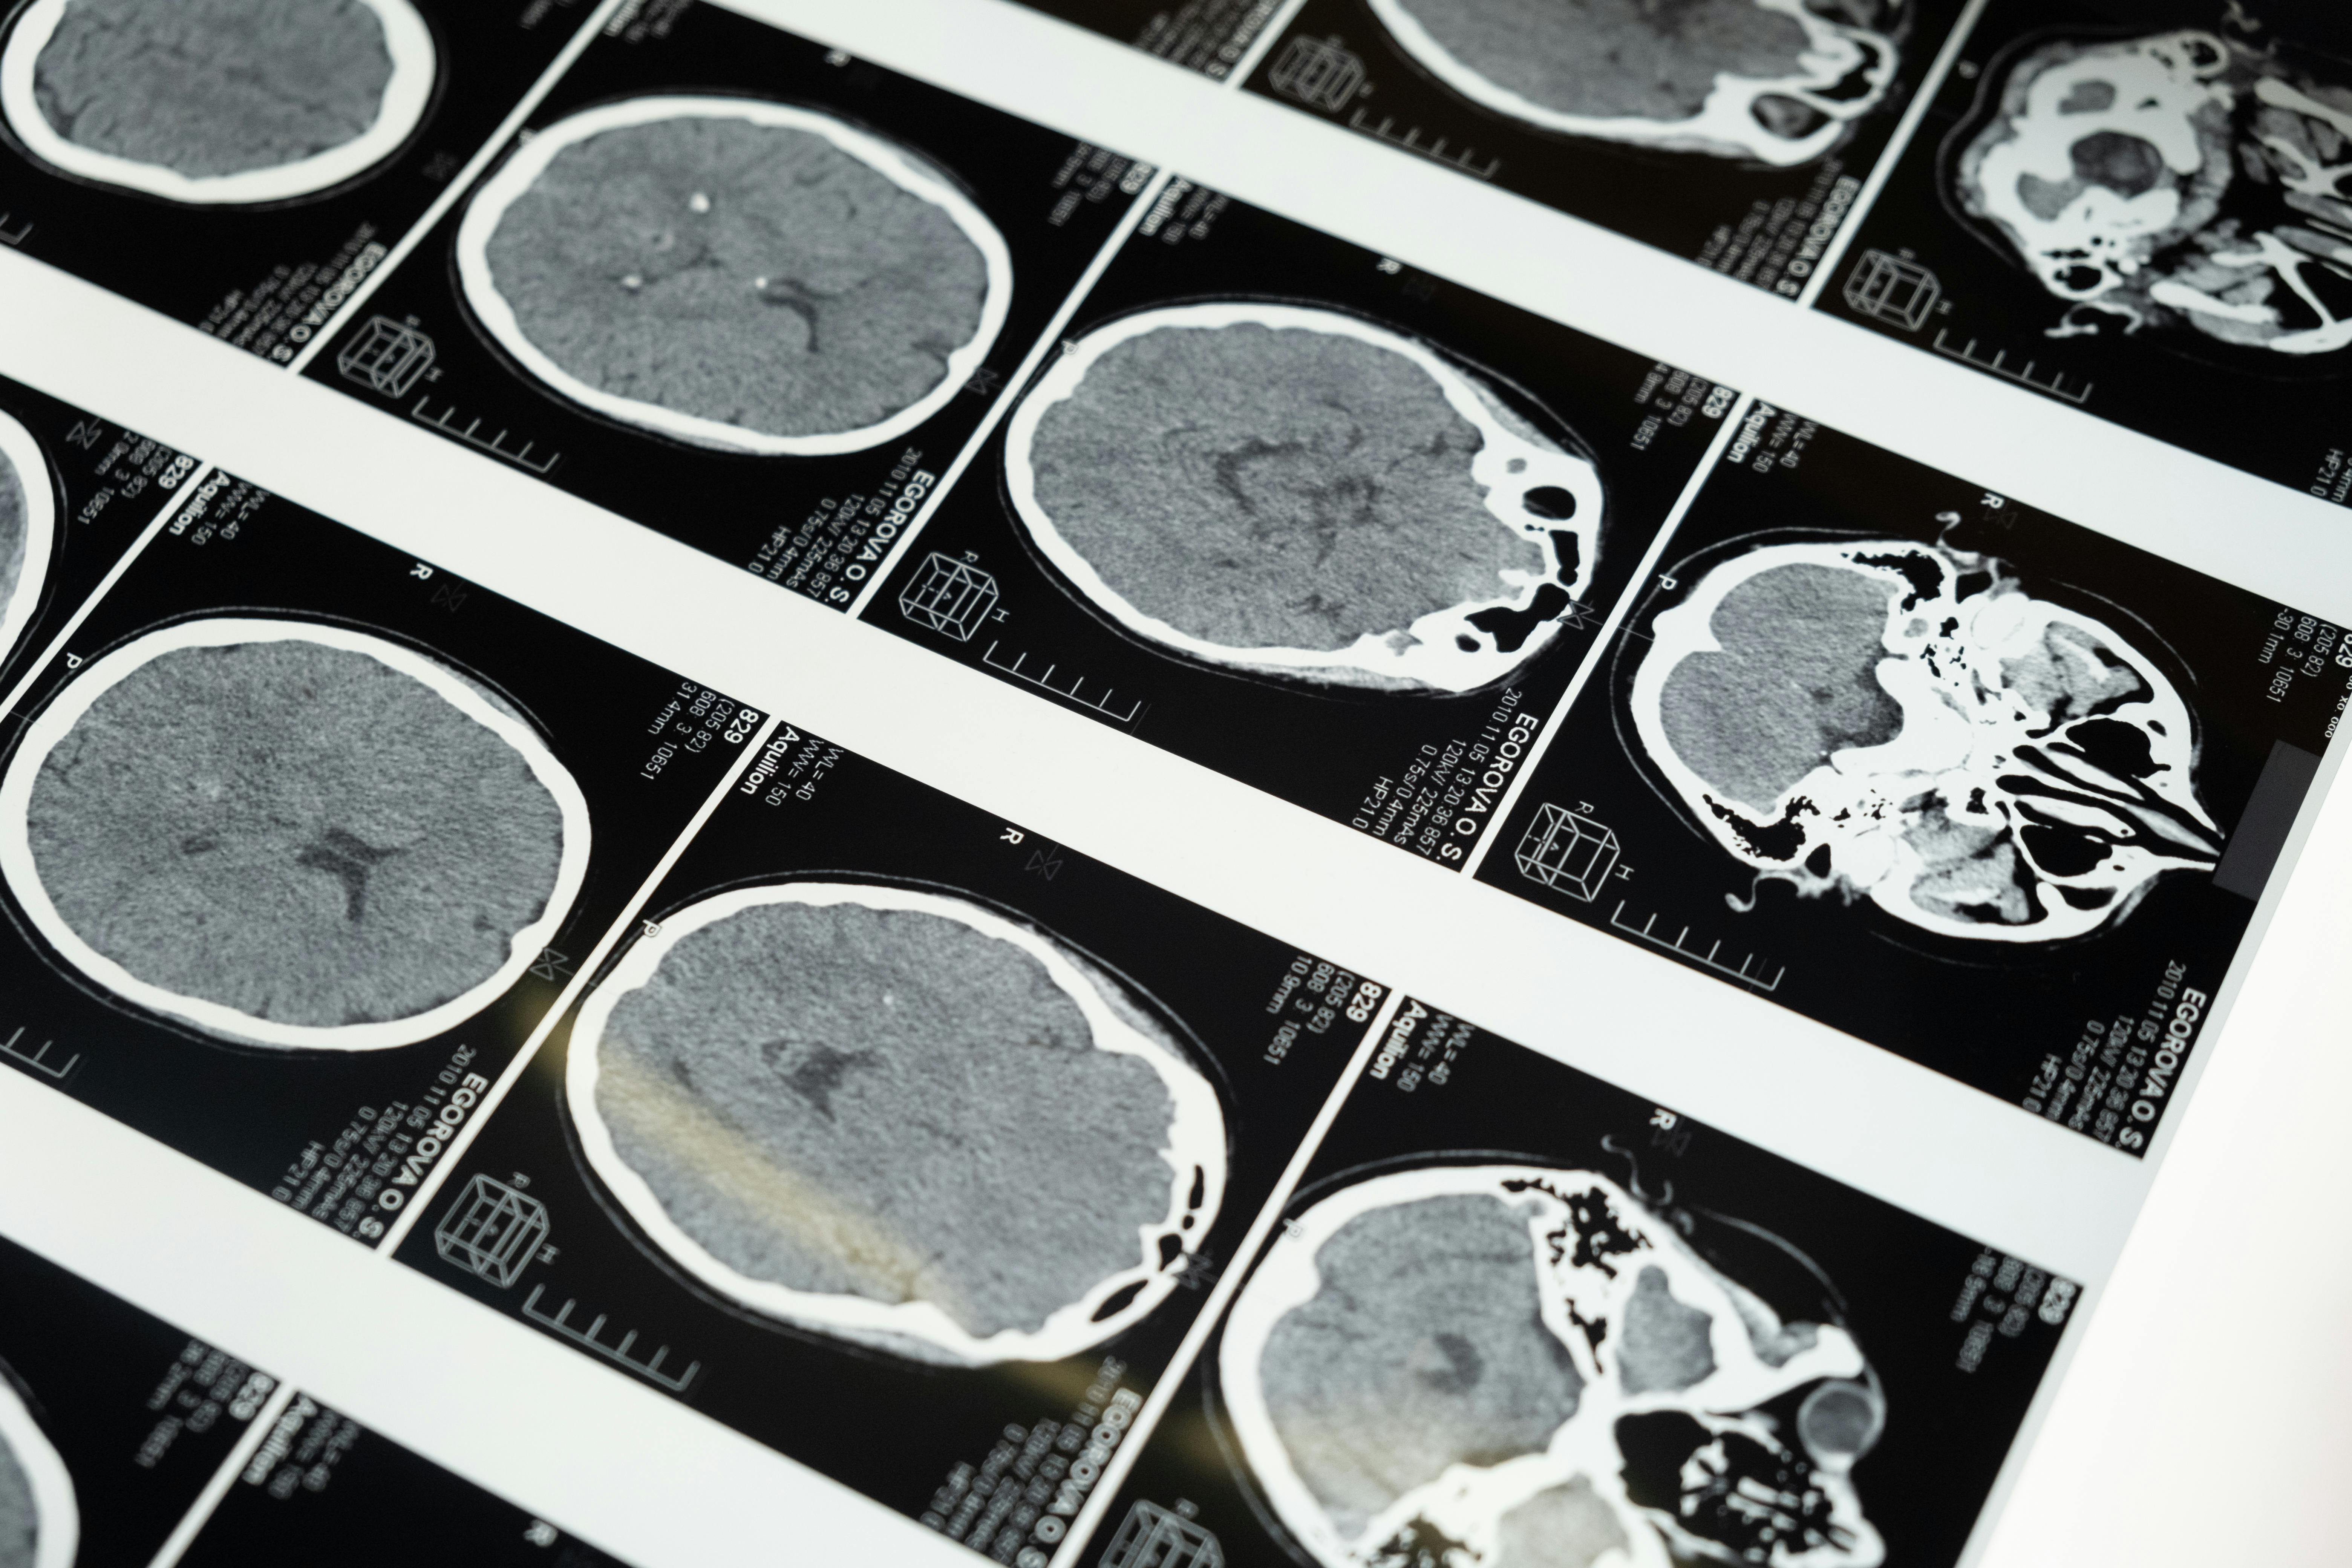

Technologies and study methods: include techniques such as functional magnetic resonance imaging (fMRI), electroencephalography (EEG), and high-resolution microscopy, which allow the observation of brain activity and neural structures in great detail.

Clinical and therapeutic applications: focuses on using neuroscientific knowledge to develop treatments for neurological, psychiatric, and neurodegenerative disorders, as well as improving the quality of life of people with brain injuries.